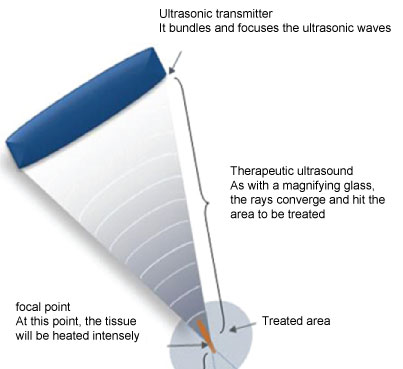

You will lie in an MRI machine to gather highly detailed images of the inside of the body. You will also receive a catheter to drain your bladder during the procedure. Your abdomen will be shaved and cleaned with alcohol to prevent burns. You will be given sedation medication to help you relax, but you will be awake and able to communicate during the procedure (often called conscious sedation). The treatment takes about three hours, and you will be able to go home a few hours after the procedure is over. This non-invasive procedure destroys fibroid tissue using ultrasound waves. What to Expect During MR-Guided Focused Ultrasound

Be sure to tell your doctor or nurse if you feel skin pain during the procedure. Your care team will take all possible precautions to prevent burns. There is a small risk of skin burns from the ultrasound heat. If you are pregnant, have certain implants (such as a pacemaker or neurotransmitter), have a blood clotting condition or other underlying health conditions, you should not receive MR-focused ultrasound treatment for fibroids. ConsiderationsĪs a minimally invasive surgery, the complications and recovery time are minimal. They are then evaluated by a team of fibroid specialists to determine if they are suitable candidates for MR-focused ultrasound. No scars and short recovery because it is a non-invasive procedureĪt the Weill Cornell Medicine Fibroid and Adenomyosis Program, all patients receive an extensive evaluation, including physical examination and fibroid mapping.Protection of healthy tissue, including the uterus and ovaries.Relief from fibroid symptoms within three to six months.The benefits of MR-guided focused ultrasound for fibroids include: MR-guided focused ultrasound is a highly effective treatment for many patients. Who Is an Ideal Candidate for MR-Guided Focused Ultrasound? The interventional radiology experts at Weill Cornell Medicine are also studying this technique for treating breast, prostate, brain, and bone cancers. This procedure is approved by the US Food and Drug Administration for treating fibroids. The interventional radiologist uses these images to pinpoint the fibroids and treat them with focused ultrasound energy, which heats the fibroids to destroy them. The procedure - often referred to as MR-guided focused ultrasound or MRgFUS - is performed by an interventional radiologist.Īn MRI provides detailed imaging of the uterus and fibroid tumors. Magnetic resonance-guided focused ultrasound is a non-invasive procedure to treat fibroids. Stronger Together in the Face of COVID-19.Coronavirus (COVID-19) Toggle Coronavirus (COVID-19) menu options.Your Rights and Protections Against Surprise Medical Bills.Advancing Patient Care Toggle Advancing Patient Care menu options.About Doctors at WCM Toggle About Doctors at WCM menu options.Myra Mahon Patient Resource Center Toggle Myra Mahon Patient Resource Center menu options.